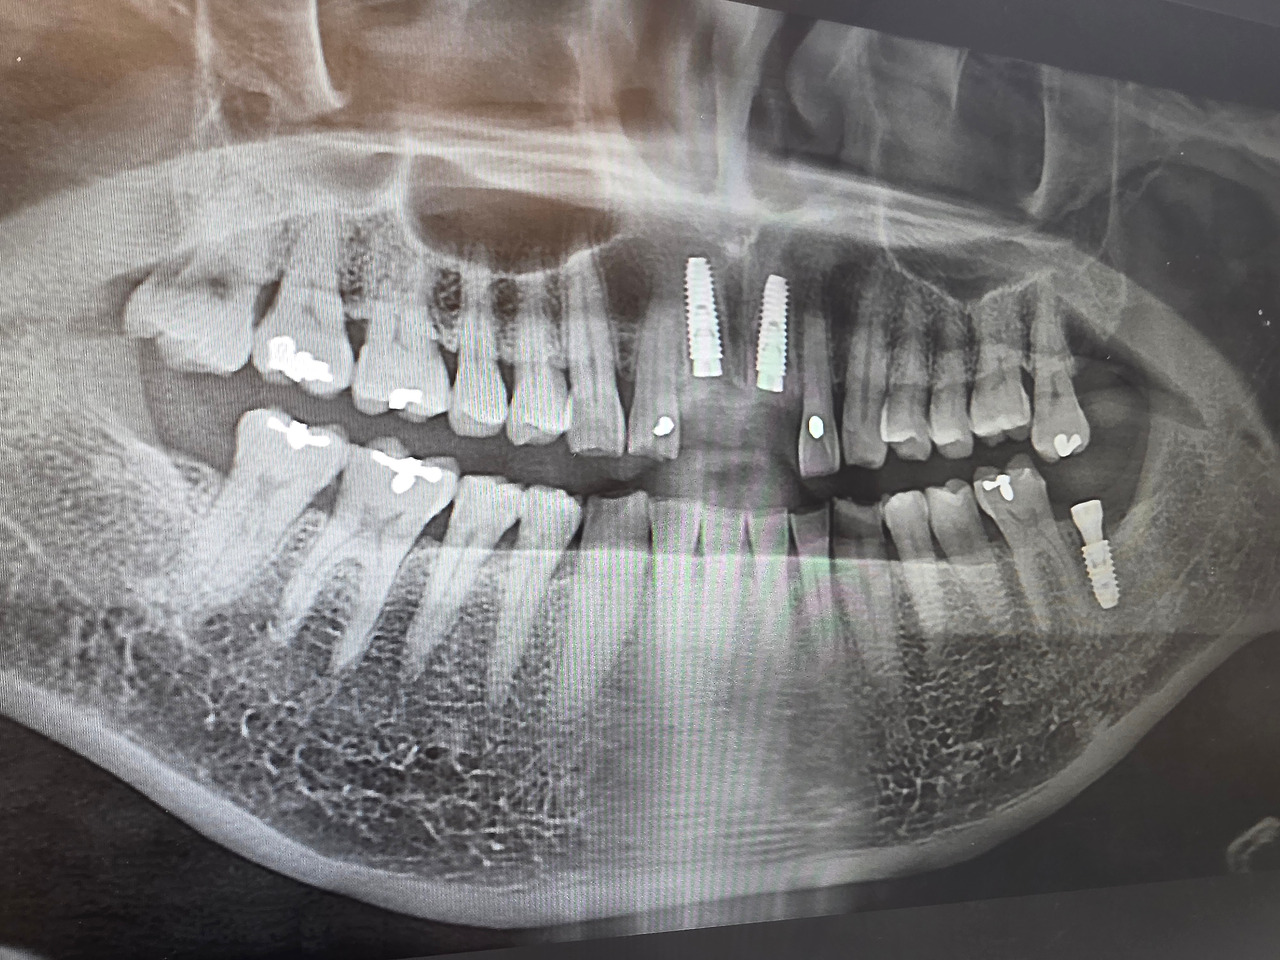

센트럴치과의 진료 과정은 정밀했다. 디지털 X-ray와 3D CT 촬영으로 사랑니 위치와 신경과의 거리, 발치 난이도를 꼼꼼히 확인했다. 설명도 알기 쉽게, 환자가 불안해하지 않도록 차분하게 해 주었다.

임플란트 수술, 정밀 기기의 힘

결국 남은 한 치아는 임플란트 수술이 필요했다. 임플란트라고 하면 많은 이들이 “비용이 크다, 통증이 심하다, 회복이 오래 걸린다”는 두려움을 갖는다. 나 역시 마찬가지였다. 하지만 동탄센트럴치과에서의 경험은 달랐다.

정밀 진단 : 3D CT 촬영으로 잇몸뼈의 두께와 신경 위치를 파악하고, 컴퓨터 가이드 수술 계획을 세웠다.

정밀 수술 기기 : 디지털 내비게이션 시스템을 통해 정확한 위치에 식립이 가능했다. 이는 수술 시간을 단축하고, 회복 속도를 빠르게 해 주었다.

통증 관리 : 수술 중 체계적인 마취와 사후 관리로 불편함을 최소화했다.

시술 후 붓기와 통증은 예상보다 훨씬 적었고, 일상 복귀도 빠른 편이었다. “임플란트 수술이 이렇게 달라질 수 있구나”라는 생각이 들 정도였다.